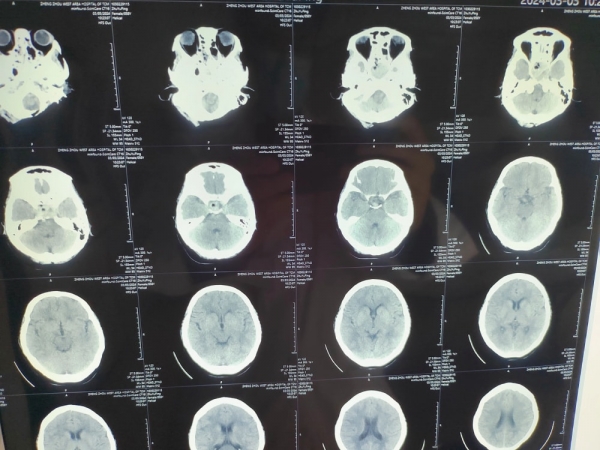

經(jīng)過檢查發(fā)現(xiàn)孫女士的發(fā)展顱內(nèi)頂葉占位性病變,需要手術(shù)進(jìn)行治療。又是一臺腦瘤手術(shù)?話音未落,張院長立刻說到,做腦科醫(yī)生的走的就是這條路,走,為患者檢查身體,制定方案,跟患者家屬溝通手術(shù)······